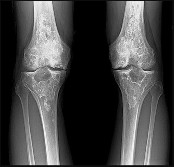

Figures 7a through 7d are the radiograph, MR images, and biopsy specimen of a 35-year-old man who has a painful, slowly enlarging knee mass. Which chromosomal translocation is characteristic of this pathology?

Synovial sarcoma is a soft-tissue sarcoma that usually occurs in young adults. Synovial sarcoma often causes pain, unlike most soft-tissue sarcomas, which generally do not cause pain. Imaging characteristics include soft-tissue calcifications on plain radiographs and a heterogeneous mass that is generally isointense to muscle on T1-weighted images and hyperintense to muscle on T2-weighted images. There are biphasic and monophasic types of synovial sarcoma. The biphasic

type, which is depicted here, has both spindle cell and epithelial components and will stain for both vimentin and cytokeratin. More than 90% of patients with synovial sarcoma have a characteristic genetic translocation of t(X;18), which results in the fusion protein SS18-SSX. This translocation can be stained for use of florescence in situ hybridization technology. t(11;12) is seen in Ewing sarcoma. T(9;22) is seen in extraskeletal myxoid chondrosarcoma. t(12;16) is seen in myxoid liposarcoma.